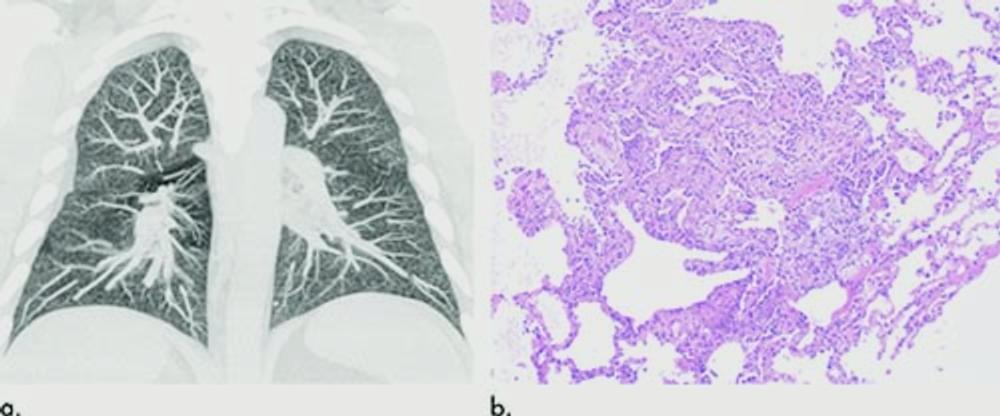

Figure 6. Images show electronic cigarette or vaping product use–associated lung injury in a 32-year-old man with history of vaping who presented with fevers and night sweats for 1 week. (a) Coronal maximum intensity projection image shows diffuse centrilobular nodularity. (b) Histologic sections of his transbronchial cryobiopsy showed distinctive micronodular pattern of airway-centered organizing pneumonia, corresponding to centrilobular nodularity seen at CT. Similar imaging and pathologic findings have been described in patients with smoke synthetic cannabinoids.

High-res (TIF) version